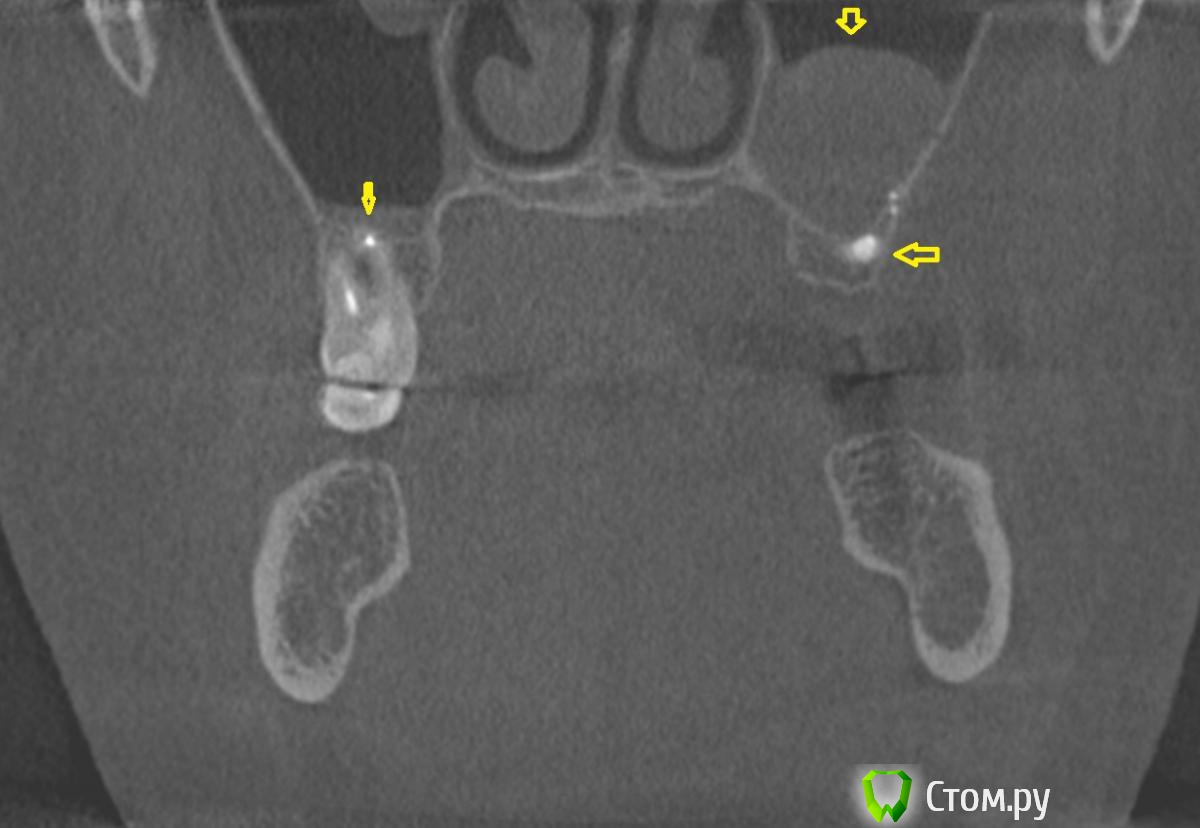

dr-krasnov Опубликовано 10 июня, 2014 Поделиться Опубликовано 10 июня, 2014 Добрый день. На томограмме ретенционная киста слева, одонтогенный синусит справа, замыкательная кортикальная пластина в области корня уже отсутствует. (желтые стрелки) С моей точки зрения необходимо эндоперелечивание причинного зуба. К лору можно сходить за рекомендациями по поводу ретенционной кисты. Обычно с ними ничего не делают, пока они не беспокоят. 1 Ссылка на комментарий

dr-krasnov Опубликовано 10 июня, 2014 Поделиться Опубликовано 10 июня, 2014 (изменено) Тэкс, посмотрел КТ. Претензий к лечению зуба не имею. 4й канал найти не удалось. То был ограниченный артефакт от запломбированного канала. Связи между этим зубом и реакцией слизистой скорее всего нет. Да и синусита нет. Изменения слизистой скорее имеют гиперпластическую природу. Источником исходных реакций послужили уже отсутствующие зубы. Архивные снимки расставили бы все точки над и. Несколько картинок: Небный на осях, можно придраться к незначительному расширению периодонтального пространства апикально, но я бы не стал http://s018.radikal.ru/i515/1406/b8/d712dd4f6158.jpg Дистальный щечный http://s020.radikal.ru/i710/1406/4f/990608ed482a.jpg Мезиальный щечный http://s018.radikal.ru/i518/1406/52/534d8d8534ec.jpg В общем, признаков периодонтита не вижу, рентгенологических показаний для резекции тоже.Я бы порекомендовал динамическое наблюдение. Изменено 10 июня, 2014 пользователем dr-krasnov 1 Ссылка на комментарий